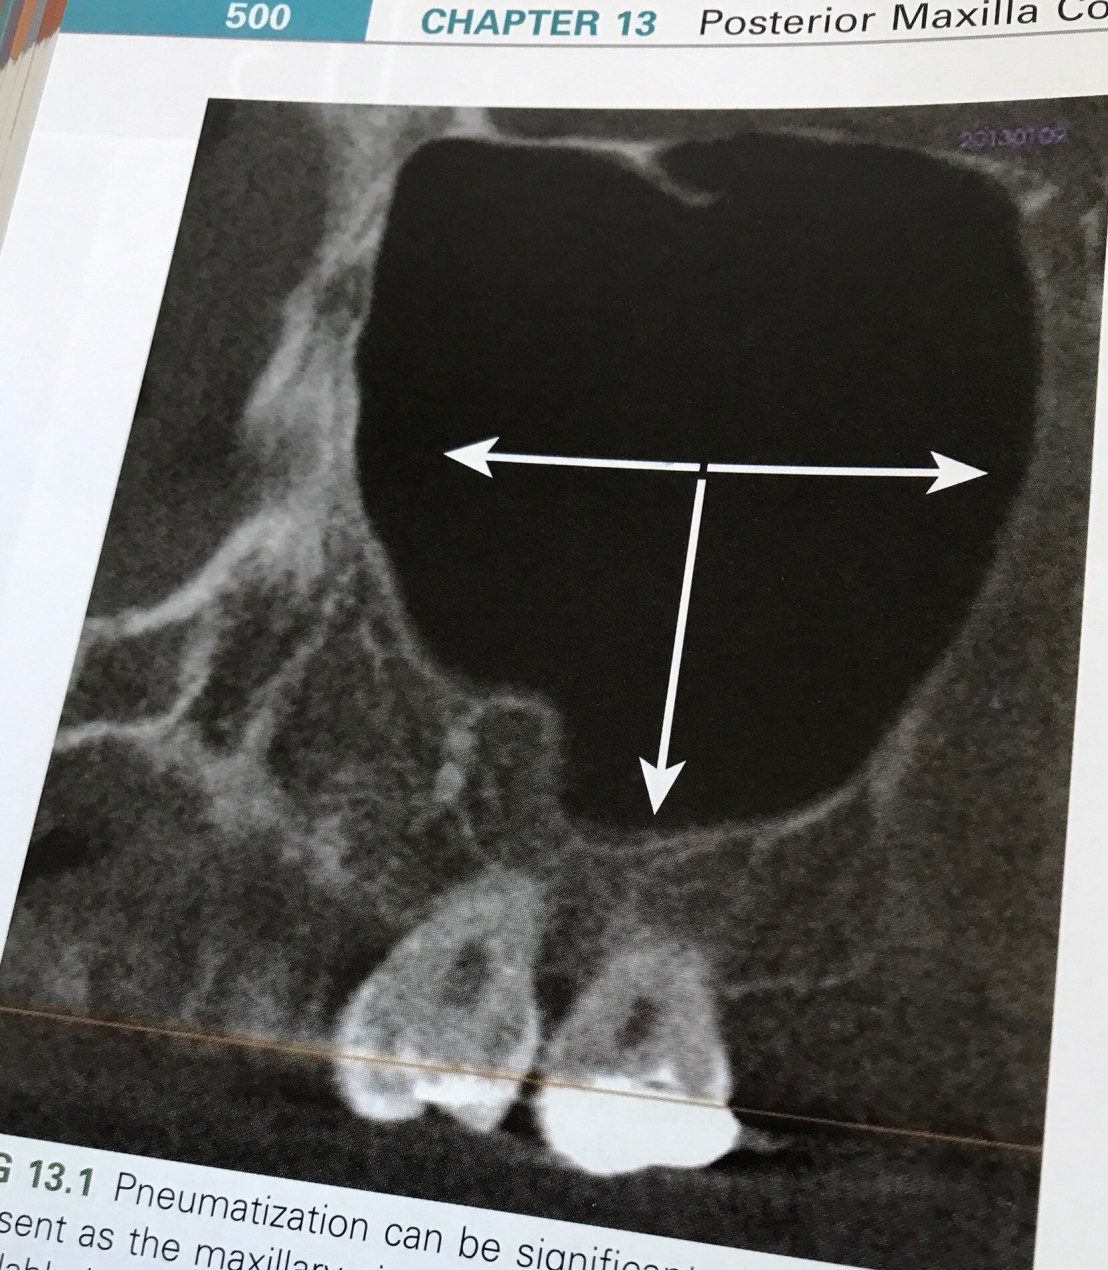

แสดงปริมาณ Bone ที่เราต้องคำนึงใน 3 มิติ ที่นอกจากจะมีผลต่อ diameter และความยาวของ Implant แล้ว ยังต้องคำนึงถึง angulation ของแรงที่ทำต่อ Implant ด้วย

กลไกการขยายขนาดของ Max sinus หลังฟันหลังบน missing จากการเพิ่มของ Osteoclastic activity ภายใน Schneiderian membrane (Periosteum ที่บุรอบ Max sinus) ทำให้ช่องว่างนี้ขยายใหญ่ขึ้น